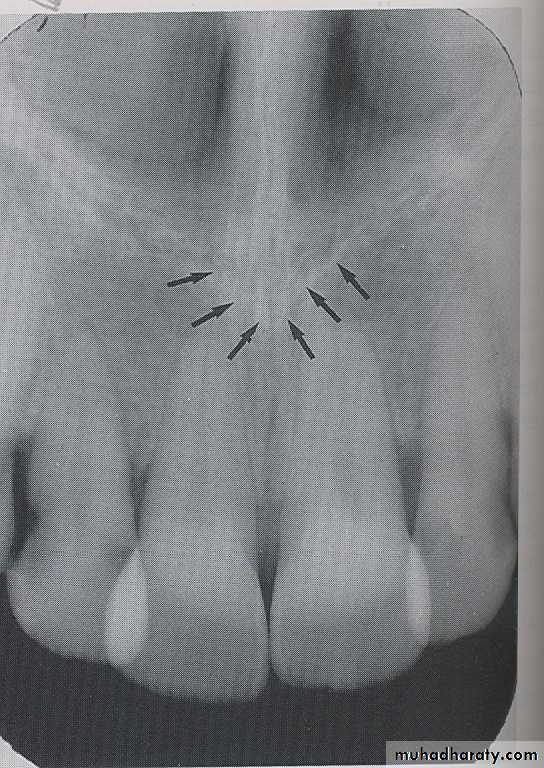

INCISIVE FORAMEN: The incisive foramen is an opening in the bone that is located at the midline of the anterior portion of hard palate. Radiographically the incisive foramen appears as a small ovoid or round radiolucent area located between root of maxillary central incisor.

The superior foramina of the incisive canal are two tiny openings or holes in bone that are located on the floor of the nasal cavity. The superior foramina are the openings of two small canals that extend downward and medially from the floor of the nasal cavity. These two small canals join together to form the incisive canal and share a common exit, the incisive foramen.Appearance. On a maxillary periapical image, the superior foramina appear as two small, round radiolucencies located superior to the apices of the maxillary central incisors